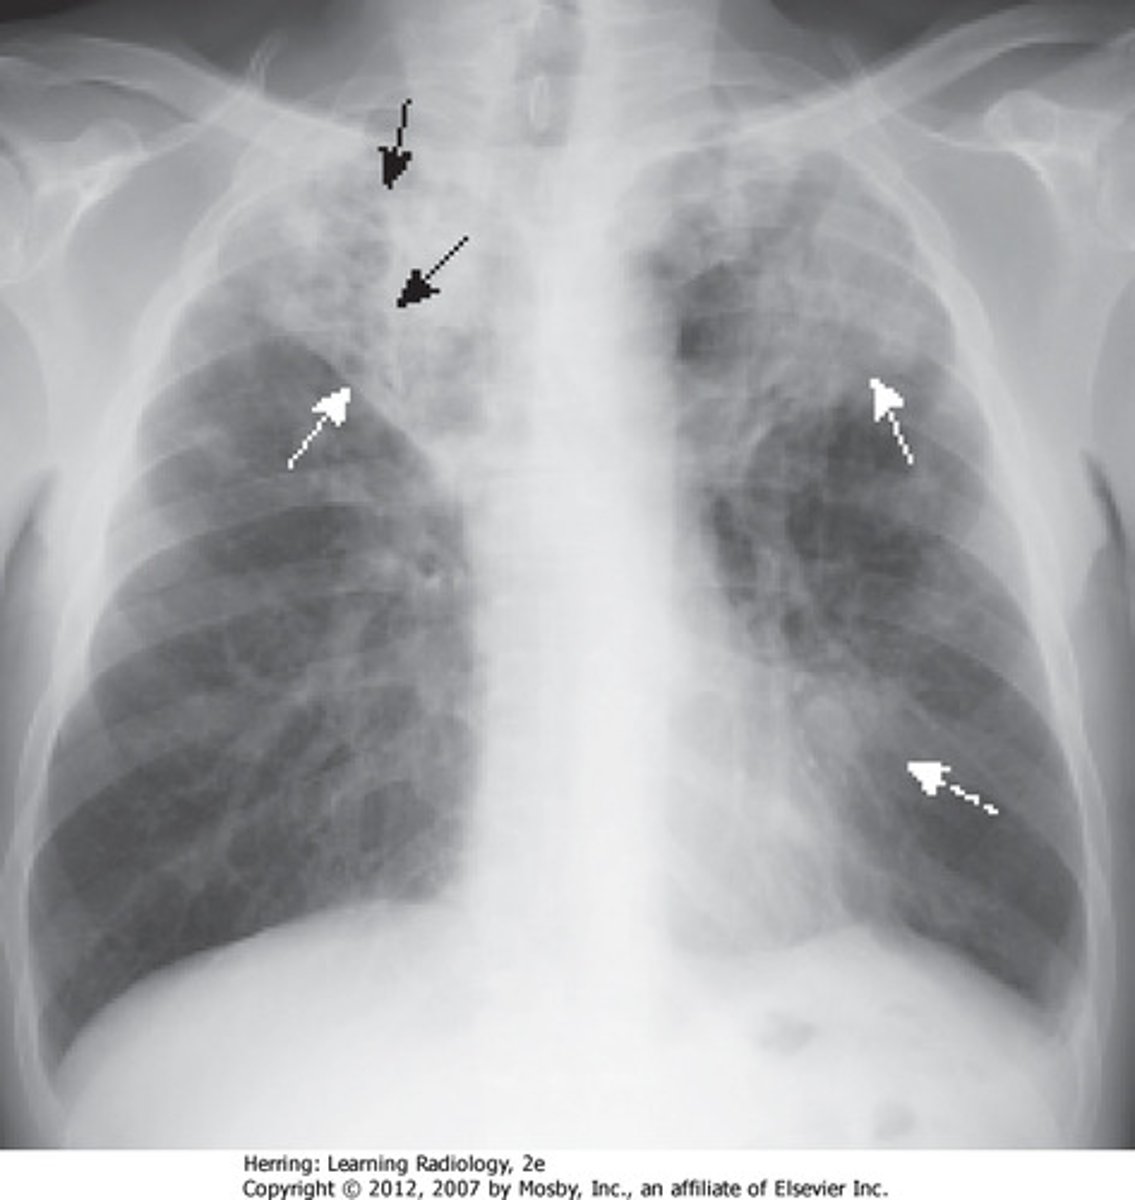

Methylmercury

A highly toxic heavy metal that biomagnifies in aquatic ecosystems and contaminates humans largely through eating of [shell]fish; damages the central nervous system (esp. children/embryos) and leads to impaired coordination and sense of touch/taste/sight.

![<p>A highly toxic heavy metal that biomagnifies in aquatic ecosystems and contaminates humans largely through eating of [shell]fish; damages the central nervous system (esp. children/embryos) and leads to impaired coordination and sense of touch/taste/sight.</p>](https://knowt-user-attachments.s3.amazonaws.com/9a69885e-2a59-4488-a53d-dadcf61ff10c.jpg)